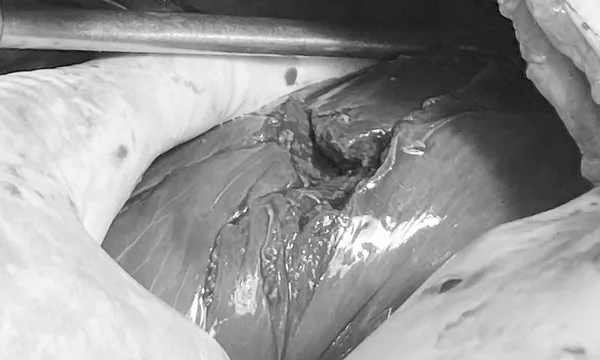

Tiến sĩ, bác sĩ Vũ Đức Thụ - Trưởng Khoa Ngoại Tiêu hóa và Tổng hợp, người trực tiếp phẫu thuật cho người bệnh cho biết, khi tiến hành mở ổ bụng của bệnh nhân có rất nhiều máu, khoảng 2.500 ml máu cục và máu loãng.

Nửa gan phải của bệnh nhân bị dập nát, nhiều đường vỡ đi khắp mặt và nhu mô gan, trong đó có 1 đường vỡ gây rách tĩnh mạch cửa phải (là một mạch máu rất lớn của gan) khiến máu chảy ồ ạt vào ổ bụng.

Ê kip phẫu thuật đã nhanh chóng cầm máu gan bằng các thủ thuật chuyên khoa sâu và khâu lại mạch máu, nhu mô gan cho người bệnh. Ca phẫu thuật diễn ra trong gần 3 giờ, sau ca mổ, sức khỏe bệnh nhân dần ổn định.